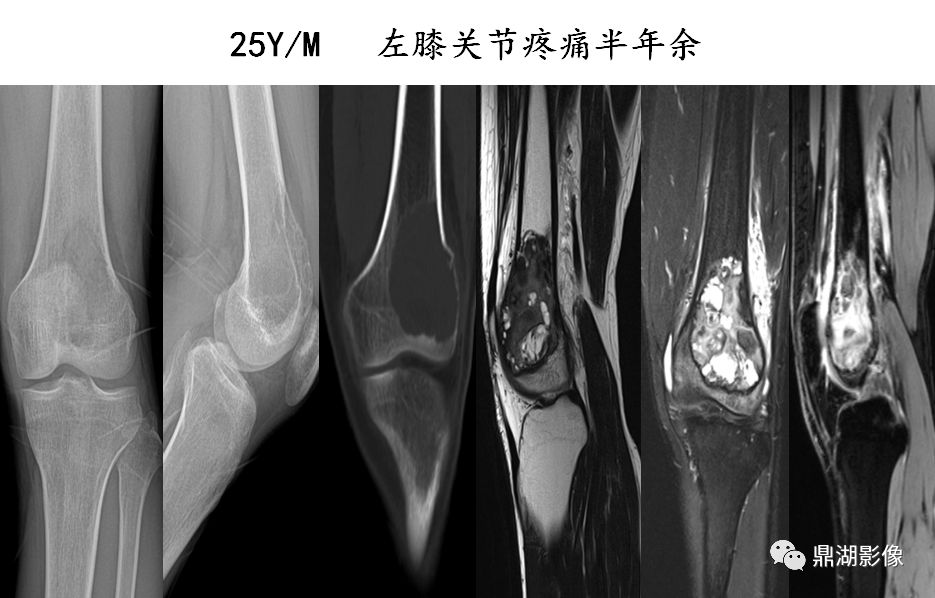

中公解析:骨肉瘤典型的x线表现为codman三角,为三角状骨膜反应阴影.

云絮状瘤骨,骨膜反应和codman三角,软组织肿块分类:成骨型,溶骨型

骨肿瘤病例讨论